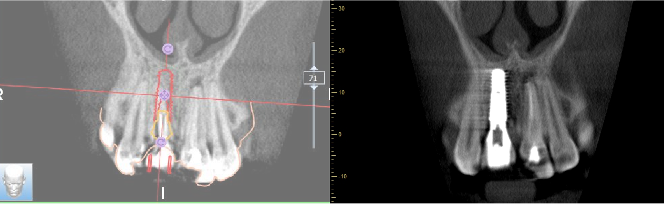

• Bilan 3D ou Tomographie volumique à faisceau conique ou Cone Beam Computed Tomography (Photo 4)

Sur le cone beam réalisé nous retrouvons bien notre lésion latérale au niveau de 11 et notre lésion apicale au niveau de 21. A noter également la fracture palatine du tiers cervical radiculaire.

On note la présence d’une paroi osseuse vestibulaire intacte permettant d’envisager une extraction

atraumatique suivie d’une implantation immédiate, dans de bonnes conditions.

Le CBCT réalisé (fichiers dicom) est inséré dans le logiciel RealGuide pour permettre de l’associer avec

l’empreinte numérique de la patiente (Photo 8). Ces éléments nous permettent donc de simuler :

• L’avulsion de la dent 11

• L’évaluation des parois osseuses résiduelles

• La position implantaire idéale, en respectant l’axe prothétique et les contraintes anatomiques.

Un CBCT de contrôle est réalisé en fin d’intervention pour permettre de visualiser que la position implantaire correspond exactement à la planification réalisée (Photo 16).